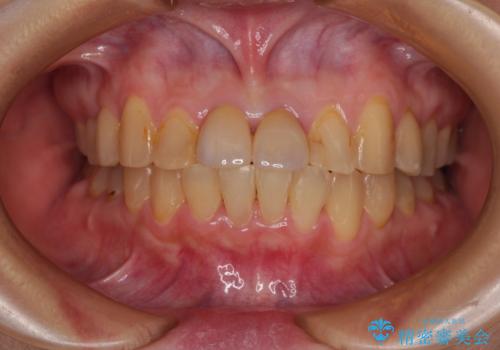

前歯のデコボコをワイヤー矯正で速やかに改善

- 前歯のデコボコを気にして来院された患者様です。

安価に速やかに治療をしたいとのことで、メタルワイヤーにより矯正治療を行うこととしました。